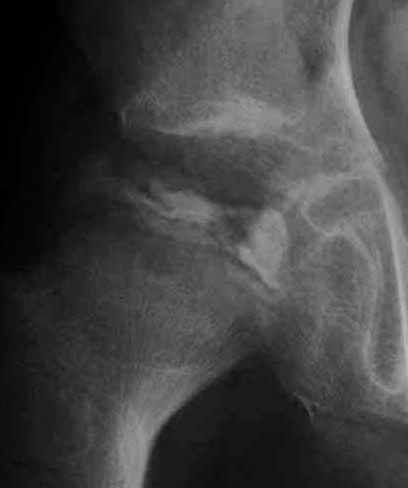

2)骨盤骨切り術(ソルター手術)。骨盤骨の一つである腸骨を人工的に骨折させ臼蓋の向きを変えて骨頭を包み込む手術です。下肢短縮はおこりませんが、臼蓋を下方へ下げて骨頭を圧迫する為に、骨形成にとっては不利な面があります。

右図のように、骨盤の骨切りをおこなって十分骨頭を包み込みます。この手術のコツは、骨盤骨を広範に剥離すること、臼蓋を回転させるときに細かい技を駆使することです。この手術も慣れた術者がしなければなりません。経験上、100例くらい経験すると洗練された手術ができるようになると思います。

上図は10歳男子で、装具療法がうまくゆかないまま放置されていた例で、著しい変形があった例です。